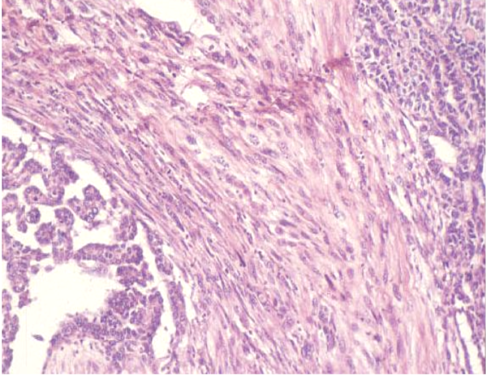

二相型胸膜中皮腫の病理像(HE染色)

上皮様増殖と肉腫様増殖が混在する典型的な二相型中皮腫